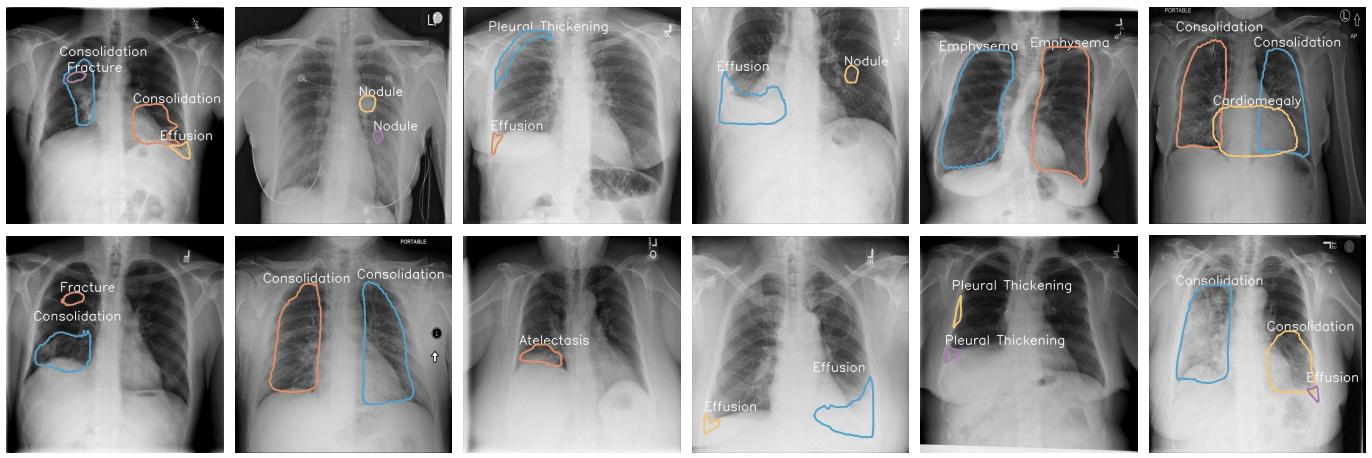

What do we look for in a CXR?

• How about this one?

Cardiomegaly - A big heart

• Water where it is not supposed to be.

Pleural Effusion